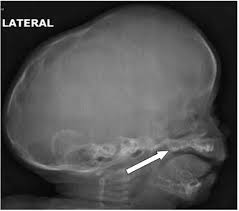

'copper beaten' skull refers to the prominent convolutional markings seen in multiple bones of the skull. Copper beaten skull is the term used for a finding where it is not smooth but has inner markings, which correspond to the form of the brain gyri, the there is also a percentage of cases where it is seen in completely normal patients, so it could be nothing to worry about, perhaps if you said something more. Skull radiograph demonstrates multiple small radiolucent areas with relatively round radiopaque markings around them, in a pattern similar to the at produced by beating on a sheet of metal with a small mallet. The ore is concentrated by froth flotation process. Even today, a lot of jewellery in india is.

The cbk appearance is typically associated. The appearance is called copper beaten skull or brass beaten skull. Skull radiograph demonstrates multiple small radiolucent areas with relatively round radiopaque markings around them, in a pattern similar to the at produced by beating on a sheet of metal with a small mallet. The appearance of a copper beaten skull is associated with raised intracranial pressure in children. If you continue browsing the site, you agree to the use of cookies on this website.

Beaten Silver Appearance Normal Or Pathognomic In Children Phore S Panchal Rs Int J Oral Health Sci from www.ijohsjournal.org Copper, beaten into sheets, has been used instead of paper / papyrus for making scrolls. Beaten copper appearance (hammered silver). Skull radiographs demonstrate copper beaten skull. See our user agreement and privacy policy. A diffuse beaten copper pattern on skull radiographs, along with obliteration of anterior sulci or narrowing of basal cisterns in children under the age of 18 months, is predictive of increased intracranial pressure in over 95 percent of cases tuite and lindquist, 1996. Slideshare uses cookies to improve functionality and performance, and to provide you with relevant advertising. Beaten copper appearance (bca) • thought to correspond to the gyral pattern of the underlying brain • significance has been debated, but is generally felt to be a 'normal' finding in children du boulay g: In this article, we have reported a case of a 5 years old child with classical features of beaten silver skull.

However, the copper beaten appearance of the skull has poor sensitivity in detecting increased intracranial pressure as such an appearance can also be seen in normal patients. Zurück zum zitat mahomed n, sewchuran t, mahomed z. A diffuse beaten copper pattern on skull radiographs, along with obliteration of anterior sulci or narrowing of basal cisterns in children under the age of 18 months, is predictive of increased intracranial pressure in over 95 percent of cases tuite and lindquist, 1996. Beaten copper appearance (hammered silver). Hoid appears as wit in the middle of the novel, discussing the nature of power with shallan. Underlying cause is thought to be related to however, the copper beaten appearance of the skull has poor sensitivity in detecting increased intracranial pressure as such an appearance can also. Copper beaten skull is a phenomenon wherein intense intracranial pressure disfigures the internal surface of the skull. Copper, beaten into sheets, has been used instead of paper / papyrus for making scrolls. Prior to that, while telling the story of mishim in alethkar, hoid sees something next to his pack, which startles him. Copper beaten skull is a phenomenon wherein intense intracranial pressure disfigures the internal surface of the skull. Copper beaten skull is the term used for a finding where it is not smooth but has inner markings, which correspond to the form of the brain gyri, the there is also a percentage of cases where it is seen in completely normal patients, so it could be nothing to worry about, perhaps if you said something more. Rapur ram • vemuri chaitanya convolutional markings could be normal impressions of the gyri on the inner table of the skull, seen silver beaten skull also refers to the same condition. Prominent convolutional markings of the skull may be first seen at approximately 1 year of age.

Craniofacial Diseases from www.mipediatra.com University challenge viewers are glued to their screens as st hilda's college oxford beats ucl by bbc2 quiz show university challenge saw st hilda's college oxford take on ucl st hilda's scraped a win, beating their opponents by just five points 11. Skull radiograph demonstrates multiple small radiolucent areas with relatively round radiopaque markings around them, in a pattern similar to the at produced by beating on a sheet of metal with a small mallet. However, the copper beaten appearance of the skull has poor sensitivity in detecting increased intracranial pressure as such an appearance can also be seen in normal patients. Copper beaten skull is a phenomenon wherein intense intracranial pressure disfigures the internal surface of the skull. Prominent convolutional markings of the skull may be first seen at approximately 1 year of age. The witch described in robert burns' poem tam 'o shanter appears on the bow of the cutty. However, the copper beaten appearance of the skull has poor sensitivity in detecting increased intracranial pressure as such an appearance can also be seen in normal patients. Skull radiographs demonstrate copper beaten skull.